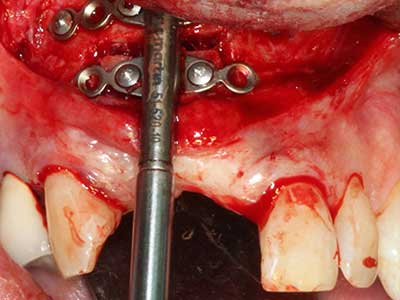

Si es preciso realizar intervenciones quirúrgicas en las que el hueso está en contacto directo con estructuras sensibles, como son los vasos sanguíneos o los nervios, los instrumentos rotativos presentan un enorme potencial de provocar lesiones iatrogénicas. Así, precisamente en la representación de nervios después de una lesión iatrogénica, o en el transcurso de la lateralización de un nervio para resecciones, reconstrucciones o incorporación de implantes, los equipos piezoeléctricos pueden resultar muy útiles para preparar la tapa ósea y retirar las partes de tejido duro cercanas al nervio (fig. 17-20). Por lo general, un ligero contacto del cordón nervioso con el inserto piezoeléctrico no tiene consecuencia alguna; ahora bien, un procedimiento poco cuidadoso con movimientos tipo sierra o piezas de trabajo sobre la base ósea aún existente puede provocar lesiones nerviosas temporales o incluso permanentes. Con todo, el riesgo de sufrir una lesión de este tipo se considera significativamente inferior que en los casos en los que se utilizan sierras y fresas (Pereira, Gealh et al. 2014).

Como ya se ha demostrado en el pasado, básicamente cualquier procedimiento de cirugía de hueso representa una posible indicación para la cirugía piezoeléctrica. Así, la preparación del segmento móvil en la osteogénesis de distracción (fig. 23-25) y en la osteotomía de sándwich puede realizarse con piezas especiales, sin poner en peligro el suministro sanguíneo de la parte crestal, que resulta esencial para el éxito de ambas técnicas (González-García, Diniz-Freitas et al. 2008).